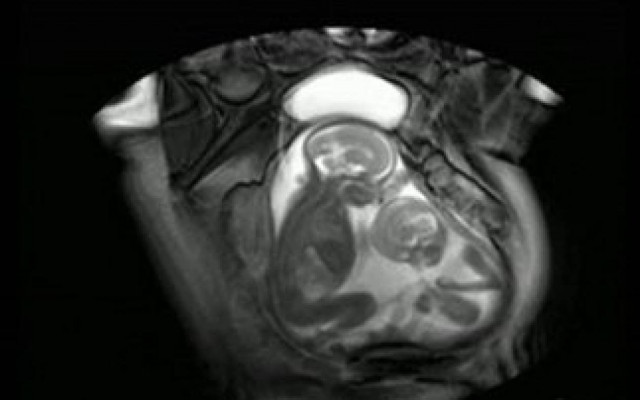

Κίνα: Γυναίκα με δύο μήτρες γέννησε δίδυμα - Ένα από κάθε μια

ΚΟΣΜΟΣ · 02.10.2024 - 10:57

Σύμφωνα με το νοσοκομείο, η νέα μητέρα γεννήθηκε με δύο τραχήλους και δύο μήτρες, πράγμα το οποίο απαντάται σε περίπου 1 στις 2.000 γυναίκες.